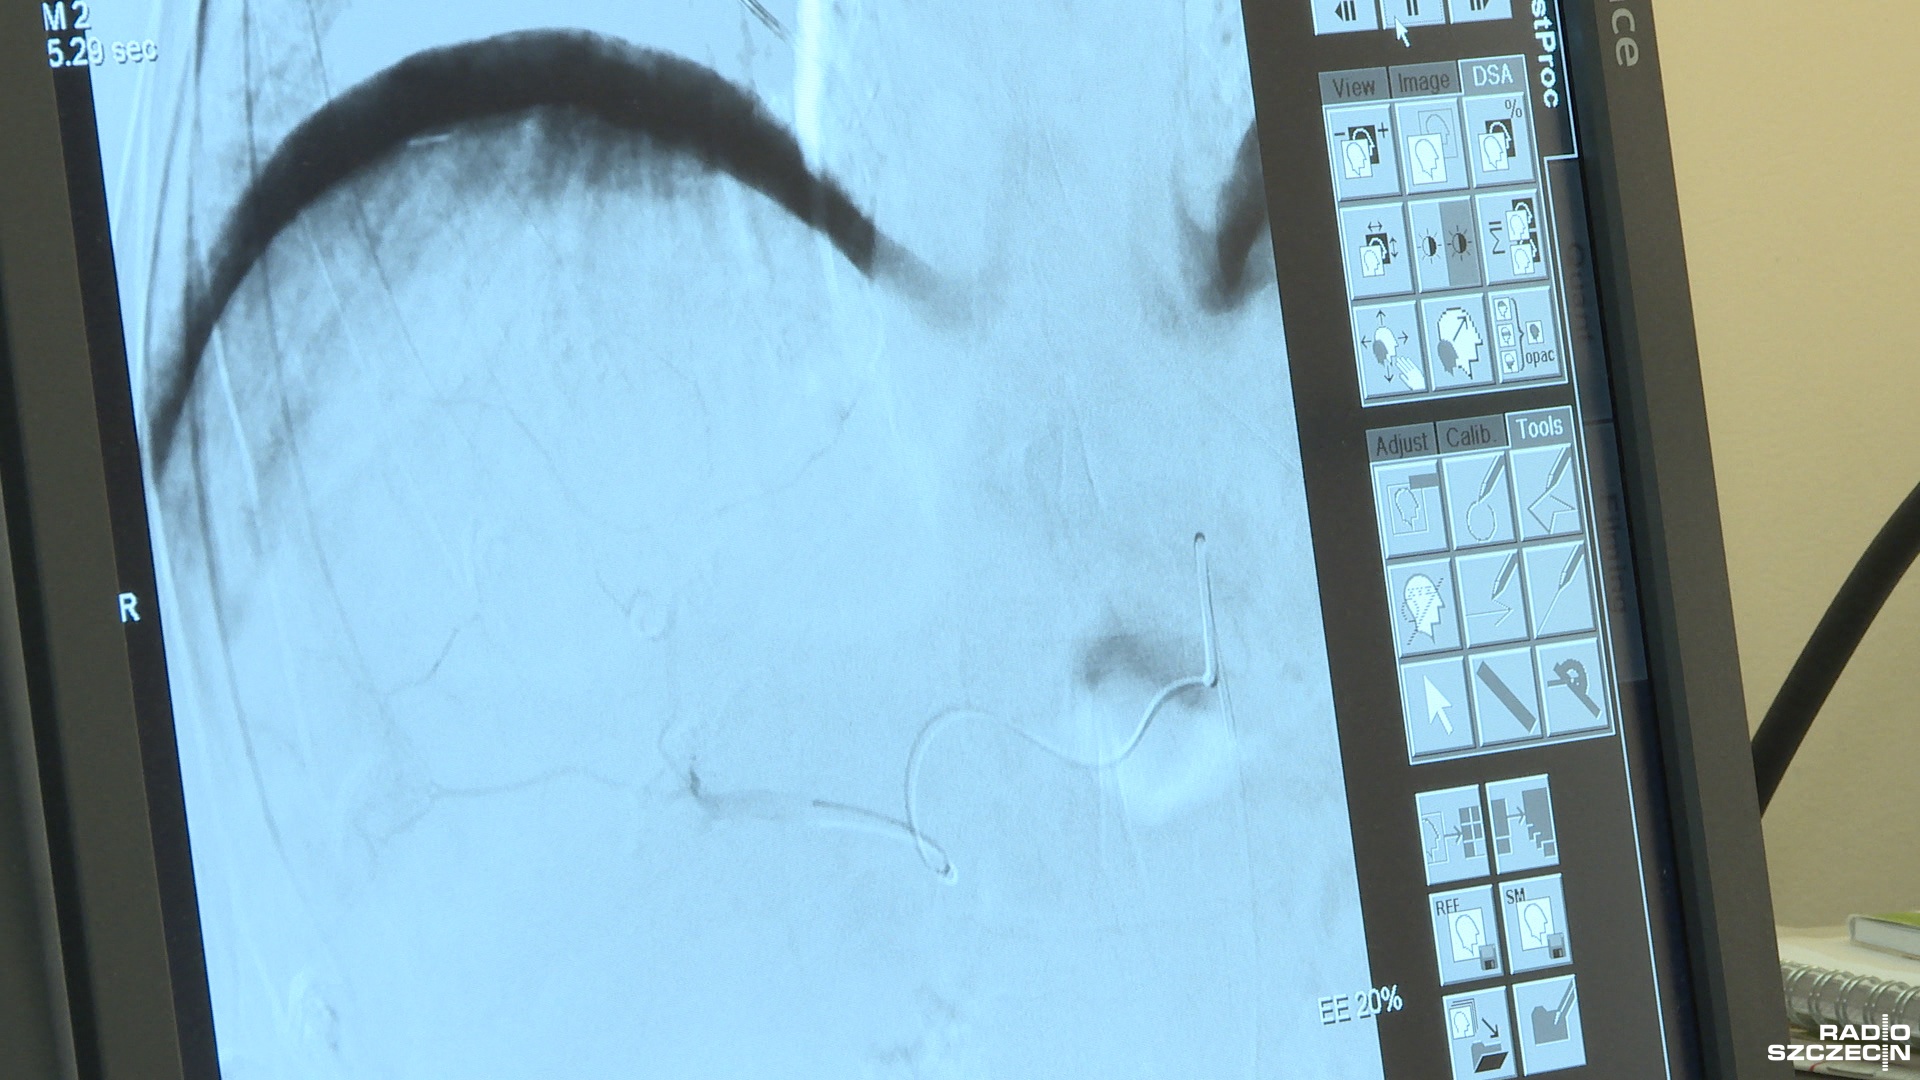

Lekarze podają chemię przez cewnik prosto w zmienione nowotworem komórki. To przynosi lepszy efekt terapeutyczny, pozwala wydłużyć życie pacjentów o kilka lat - mówi prof. Aleksander Falkowski z Zakładu Radiologii Szpitala na Pomorzanach.

- Możemy każdą zmianę nowotworową nasycić tym lekiem, nawet jeśli jest ich kilka w wątrobie. Leczyć każdą pojedynczą zmianę - wyjaśnia Falkowski.